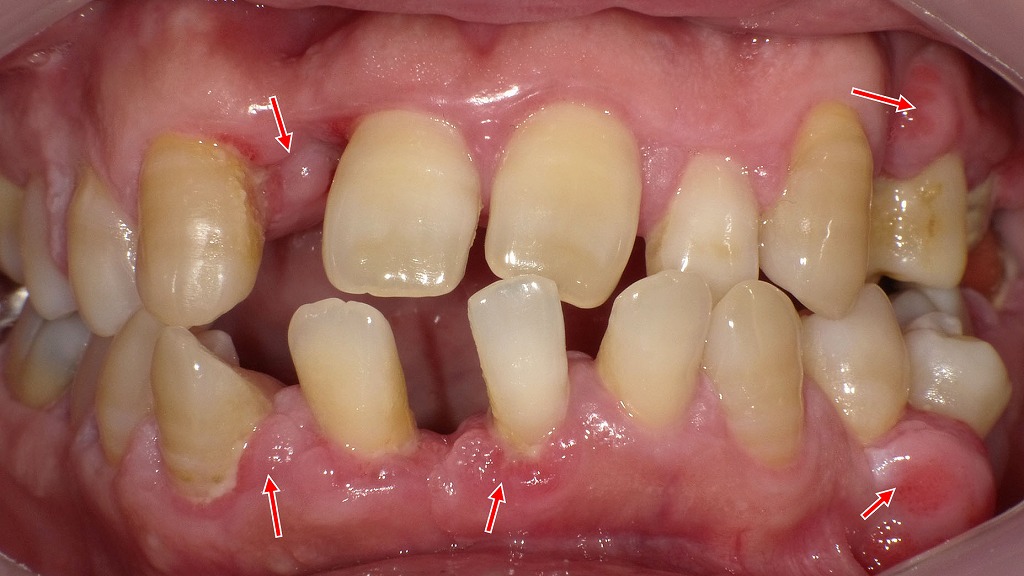

深い歯周ポケットが形成された状態 ― 重度歯周病の口腔内所見

赤矢印で示す部位では、歯ぐきの炎症が慢性化し、歯と歯ぐきの間に深い歯周ポケットが形成されています。これは重度歯周病に特徴的な所見で、歯槽骨の吸収が進行し、細菌や歯石が内部に溜まりやすい状態です。歯周ポケットが深くなるほどセルフケアでは清掃が困難となり、歯の動揺や膿の排出、最終的には歯の喪失につながるリスクが高まります。専門的な歯周治療が不可欠な段階です。